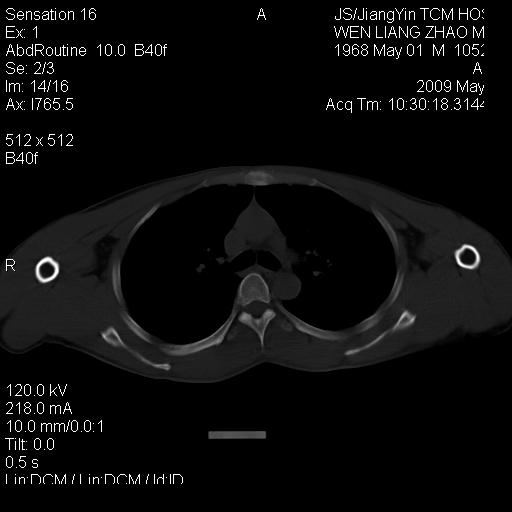

标题: CT19762:左侧喙突处压痛二年。考虑骨样骨瘤。 [打印本页]

标题: CT19762:左侧喙突处压痛二年。考虑骨样骨瘤。

左侧喙突处压痛二年。考虑骨样骨瘤。

病灶外缘膨胀明显,灶缘硬化较少,结合病史较符合骨母细胞瘤,其他亦不排除如软骨及软骨母细胞瘤等(病灶形态,成份较符合,发病部位也符合,只是年龄较大),骨样骨瘤多有较明显的自发性痛,且夜间痛明显,病史为压痛两年,不太符合.

支持骨样骨瘤(瘤巢小于1.5mm),骨母细胞瘤又称为巨大骨样骨瘤指瘤巢大于2cm的骨样骨瘤.